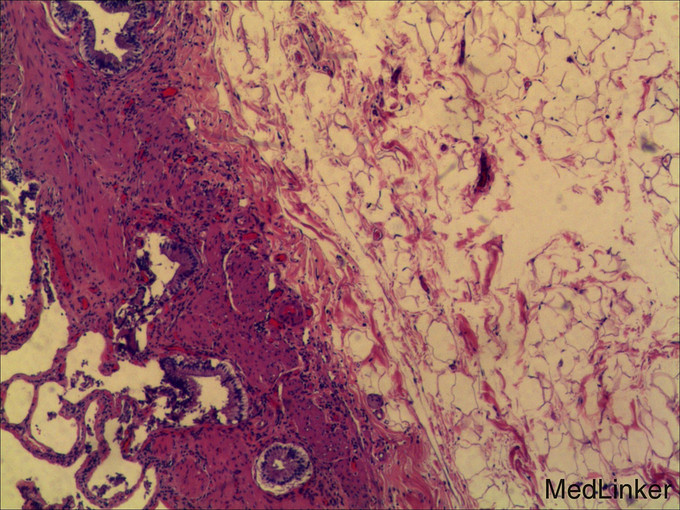

查体: 皮肤黏膜无黄染及苍白,腹部膨隆,腹肌软,未触及肝脏肋下缘,无肝震颤。 辅查: 1.腹部CT:1.肝内多发囊肿,其中右叶可见巨大囊肿。 2.胆囊结石。 3.右肾小囊肿;左肾小结石。 2.术后病检: 1(胆囊)送检5.5x2x1cm组织一块,内见结石。镜下:慢性胆囊炎,胆囊结石。2(囊壁)送检直径6cm囊壁样组织一块,囊壁厚0.1cm。 镜下:送检纤维囊壁样组织,部分囊壁披覆单层上皮,局部囊壁可见少量肝组织,病变符合肝囊肿。

术后患者有一过性肝功能异常,表现为转氨酶升高,胆红素未见明显异常,考虑手术及囊肿压迫所致;后经过对症处理逐渐恢复正常。肝囊肿属良性病变,需与肝包虫病、肿瘤相鉴别,尤其当囊液发生感染、出血、机化等继发性变化,很容易与上述疾病混淆。